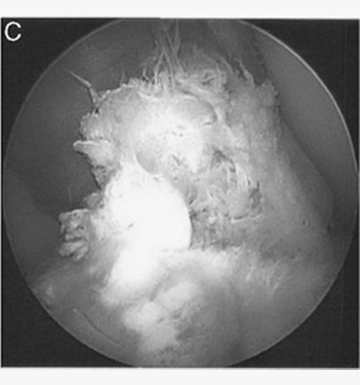

Clinical Outcomes of Inside-Out Meniscal Repair According to Anatomic Zone of the Meniscal Tear

Within the meniscus, three anatomical zones have been described based on varying levels of vascularity. The “red-red” zone is on the periphery of the meniscus and has been reported to be the most vascular, whereas the middle “red-white” and...read more